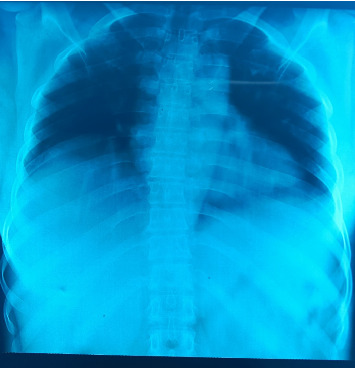

登革热是由登革热病毒四种血清型(DENV-1、DENV-2、DENV-3和DENV-4)中的任何一种引起的新出现的虫媒病毒感染,并通过伊蚊属蚊子的叮咬传播。兹报告从2023年10月22日至2023年12月5日在津德尔和尼亚美国立医院传染病科和热带病科住院的7例登革热病例。所有病例均出现发热、呕吐、疼痛和出血性综合征。全血细胞计数分析结果显示,所有患者均有血小板减少症,6例有白细胞减少症,2例有贫血。此外,还记录了1例肾衰竭。该病例在虫媒病毒国家参考实验室使用定性实时聚合酶链式反应(qRT-PCR)对血液样本进行了确认。该技术基于使用Wagner等人描述的特定引物和探针扩增四种登革热病毒核酸血清型中的任何一种。所有病例住院后均康复。

Dengue is an emerging arbovirus infection caused by any of the four serotypes of dengue virus (DENV-1, DENV-2, DENV-3, and DENV-4) and transmitted via the bite of a mosquito from the genus Aedes. We hereby report seven cases of dengue hospitalized at the infectious and tropical disease departments of the National Hospitals of Zinder and Niamey from October 22, 2023, to December 05, 2023. All the cases presented fever, vomiting, algic, and hemorrhagic syndrome. Results from the complete blood count analysis revealed that all the patients had thrombocytopenia, six cases have leukopenia and two cases have anemia. Furthermore, one case of kidney failure was recorded. The case confirmation was conducted at the National Reference Laboratory for Arbovirus on blood samples using qualitative Real-Time Polymerase Chain Reaction (qRT-PCR). The technic is based on the amplification of any of the four serotypes of dengue virus nucleic acid using specific primers and probes as described by Wagner et al. All the cases recovered after hospitalization.